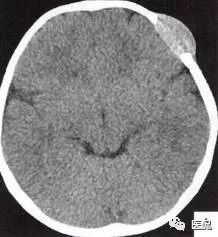

颅脑CT示:图A〜D,CT平扫示左侧额骨、蝶骨见溶骨性骨质缺损,边界清晰,周围无硬化边,伴有软组织肿块向脑外生长,边缘光滑,脑内无明显侵犯;

图E、F,横、 矢状位CT增强示软组织肿块轻度均匀强化,两病灶间亦见强化软组织影;

图G,矢状位骨窗示骨质破坏,边缘光整,无硬化边;

图H,为颅骨容积重建,提示类圆形骨质缺损,边缘光滑、整齐。

2.定位诊断:额骨、蝶骨均可见局限性骨质破坏,穿破颅骨内外板,见软组织肿块突向脑外;肿块与硬脑膜界限清楚,脑实质无侵犯;应考虑颅骨来源,向颅外侵犯。

②颅骨多处溶骨性破坏,穿透颅骨内外板;

③骨破坏无 硬化边,边缘光整,无膨胀;

④软组织肿块形态规则,边缘光滑;⑤脑膜及脑组织无侵犯, 表现为推压或移位。后三点均支持为良性肿块,结合年龄、实验室检查等,诊断不难。本例经病理(图I)证实为:嗜酸性肉芽肿。